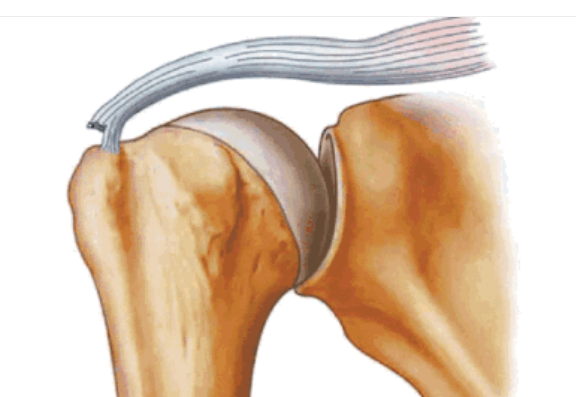

按照损伤程度分为部分撕裂( MR准确性>85% )和完全撕裂(MR准确性>95% )。

部分撕裂按照受损部位又分为滑囊面、关节面及肌腱内撕裂,在MRI上可以清晰的看到其受损部位。按照损伤深度分为1级:撕裂深度小于3mm,2级:撕裂深度在3-6mm,3级:撕裂深度大于6mm。